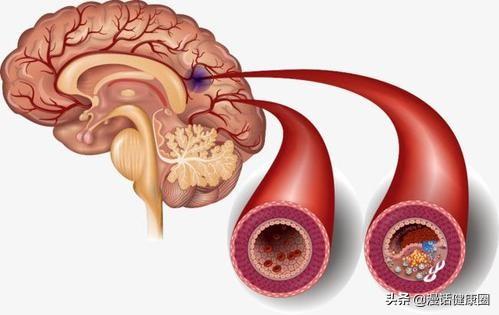

Notre cerveau gère presque toutes les fonctions de notre corps et est connu comme le commandant du corps. Le cerveau dépend du sang pour transporter l'oxygène et les nutriments dont il a besoin. Lorsque les vaisseaux sanguins sont bloqués pour diverses raisons, le cerveau est incapable d'obtenir de l'oxygène et des nutriments et meurt, entraînant la perte de fonctions de notre corps, ce qui est appelé infarctus cérébral. Les fonctions des différentes parties du cerveau étant différentes, les patients auront des séquelles plus ou moins importantes selon la localisation et l'étendue de la nécrose. Certaines personnes peuvent n'avoir qu'un léger vertige et découvrir qu'elles ont subi un infarctus cérébral lorsqu'elles se rendent à l'hôpital pour un examen (la plupart des patients atteints d'infarctus cérébral lacunaire sont découverts au cours de l'examen). Certains patients garderont des séquelles telles que l'hémiplégie, l'immobilité, la cécité, le retard mental, voire la mort.

L'infarctus cérébral est en fait un trouble de l'irrigation sanguine des vaisseaux sanguins du cerveau, qui se traduit par une irrigation sanguine insuffisante du cerveau, ce qui déclenche l'ischémie et l'hypoxie et aggrave encore la nécrose ischémique ou le ramollissement du tissu cérébral. L'infarctus cérébral représente la majorité des accidents vasculaires cérébraux dans la pratique clinique, et les types d'accidents vasculaires cérébraux les plus courants sont les suivantsThrombose cérébrale, infarctus lacunaire et embolie cérébraleetc.

L'infarctus cérébral est divisé en plusieurs types en fonction des différentes causes de l'infarctus : la rupture de la plaque causée par l'athérosclérose, formant un thrombus qui bloque les vaisseaux sanguins cérébraux, forme un infarctus cérébral ; l'embolie formée dans la région du cœur en raison d'une fibrillation auriculaire, d'un flutter auriculaire, d'une insuffisance cardiaque, d'une maladie valvulaire cardiaque, etc., qui pénètre dans les vaisseaux sanguins cérébraux avec le flux sanguin pour bloquer les vaisseaux sanguins cérébraux, forme également un infarctus cérébral ; l'occlusion des petits vaisseaux sanguins des artères cérébrales en raison d'un durcissement et de lésions, etc. forme également un infarctus cérébral, et ces infarctus cérébraux se produisent lentement en termes de pathogenèse. Ces infarctus cérébraux, bien qu'ils soient lents à se produire, mais lorsque les vaisseaux sanguins cérébraux sont soudainement bloqués, en particulier les vaisseaux sanguins importants responsables de l'approvisionnement en sang du cerveau, l'infarctus cérébral se produit d'un seul coup et il n'y a pas trop de précurseurs pour que nous puissions y faire face. L'infarctus cérébral se produit directement lorsqu'il entraîne directement dans le corps une hémiplégie, une aphasie, une ataxie, qui peuvent être accompagnées de maux de tête sévères, de nausées, de vomissements et d'autres symptômes, et l'état peut rapidement évoluer vers un infarctus cérébral. Par conséquent, pour prévenir l'infarctus cérébral, nous devrions toujours contrôler activement le risque à partir de la pathogenèse, et l'idée de se fier aux précurseurs ou aux symptômes précoces pour juger du risque d'infarctus cérébral est très difficile à mettre en œuvre pour prévenir le risque et intervenir à l'avance.

Pour l'infarctus cérébral occlusif athéroscléreux et le petit infarctus artérioscléreux, il est particulièrement important de bien prévenir l'athérosclérose et de contrôler la stabilité de la plaque. Pour ralentir le processus d'athérosclérose et protéger la santé cardiovasculaire et cérébrovasculaire, il faut tout d'abord adopter un mode de vie sain et s'y tenir, suivre un régime alimentaire sain, faire de l'exercice physique de manière raisonnable, veiller à contrôler son poids, arrêter de fumer et de boire de l'alcool, avoir de bonnes habitudes de travail et de repos et veiller à maintenir un état d'esprit calme et optimiste, ce qui est très important pour protéger la santé artérielle et réduire le risque d'infarctus cérébral. Ces aspects sont très importants pour protéger la santé vasculaire artérielle et réduire le risque d'infarctus cérébral.

La pression artérielle et la glycémie doivent être contrôlées dans une fourchette raisonnable, les lipides doivent être strictement contrôlés. Pour les patients présentant un risque élevé d'infarctus cérébral, le taux de cholestérol LDL doit généralement être contrôlé à 1,8 ou moins, afin de mieux stabiliser les plaques et de retarder le développement de l'athérosclérose. Outre le contrôle des trois taux les plus élevés, les patients atteints d'athérosclérose sévère peuvent, pour prévenir le risque d'infarctus cérébral, prendre des médicaments antiplaquettaires, tels que l'aspirine, afin de réduire le risque de formation de thrombus lors de la rupture de la plaque.